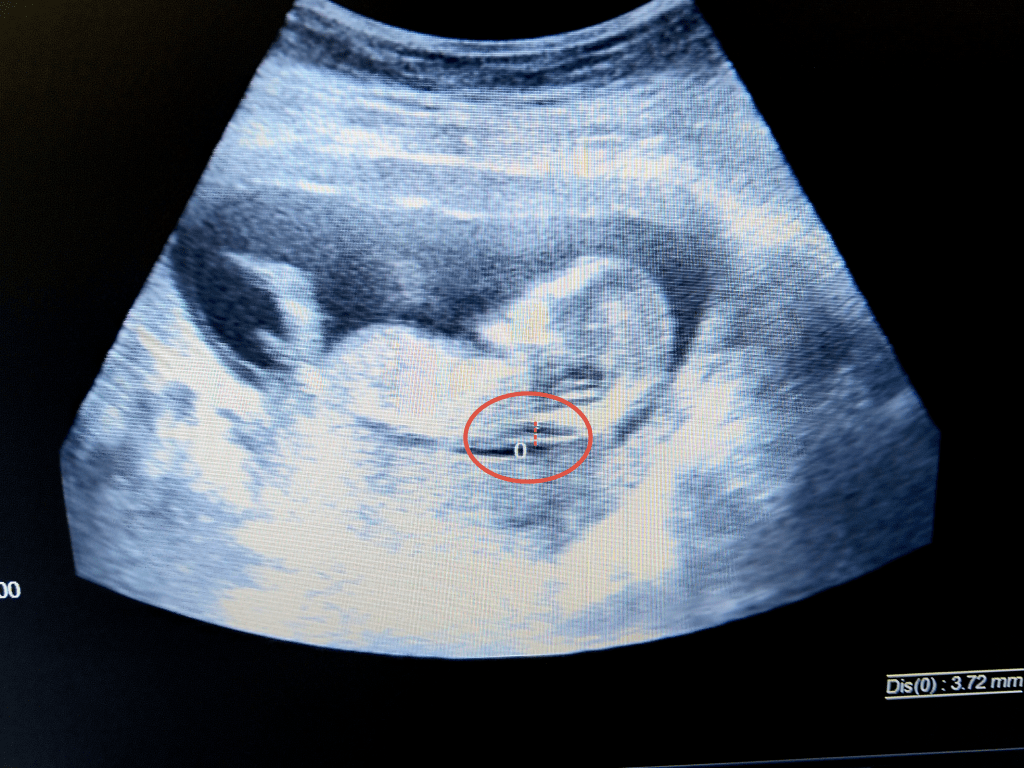

Nackuppklarningen är en vätskespalt som finns under huden vid nacken. Vätskeansamlingen kan endast registreras omkring slutet av första trimestern, mellan 11 och 14 veckors graviditet, när fostret mäter någonstans mellan 4,5 och 8,4 cm. Ju tjockare nackuppklarningen är, desto större är sannolikheten för Downs syndrom eller andra kromosomtillstånd.

Hur tjock får nackspalten vara?

Mätning av nackspalten bör inte överstiga 3 mm, men en tjock nackspalt innebär inte i sig att ett barn föds med en kromosomavvikelse. Nackspaltens tjocklek är en del av en större helhet vid riskbedömningen, eftersom din ålder och resultatet från blodprovet (dubbeltestet) alltid inkluderas i beräkningen.

Förutom att titta på nackuppviktens tjocklek kommer en nackuppviktsundersökning att visa barnets längd från huvud till stjärt, den så kallade crown rump length (CRL). Detta mått kan ibland justera ett tidigare fastställt beräknat förlossningsdatum, eftersom det vid ultraljud före vecka 20 anses att alla foster har samma storlek under de olika graviditetsveckorna.